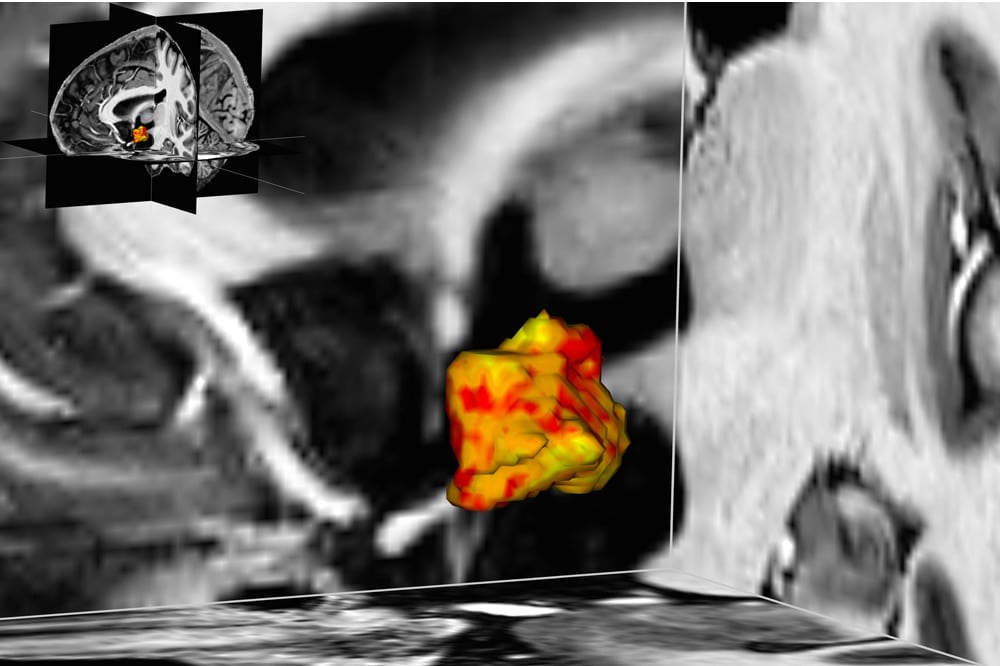

Wissenschaftler des Max-Planck-Instituts für Kognitions- und Neurowissenschaften (MPI CBS) in Leipzig und des Universitätsklinikums Leipzig haben nun in einer Studie mit insgesamt 84 Probanden herausgefunden, dass bei Personen mit einer sogenannten affektiven Störung der linke Hypothalamus um durchschnittlich fünf Prozent größer ist als bei gesunden.

„Wir haben beobachtet, dass diese Hirnregion sowohl bei Menschen mit einer Depression als auch mit einer bipolaren Störung, als zwei Formen der affektiven Störung vergrößert ist“, erklärt Stephanie Schindler, Doktorandin an beiden beteiligten Forschungseinrichtungen und Erstautorin der zugrunde liegenden Studie, die gerade im Fachmagazin „Acta Psychiatrica Scandinavica“ erschienen ist. Dabei habe sich in einer der depressiven Patientengruppen auch gezeigt, dass diese etwa ein-Cent-große Hirnregion umso größer war, je schwerer die Krankheit war.

Untersucht haben die Leipziger Wissenschaftler diese Zusammenhänge mit Hilfe der hochaufgelösten 7-Tesla-Magnetresonanztomographie. Die Schwere des psychischen Leidens ermittelten sie mit Hilfe von standardisierten Fragebögen und Interviews.

„Wir wissen bisher zwar noch nicht, welche Rolle der größere Hypothalamus innerhalb der Depression oder bipolaren Störung spielt. Frühere Studien haben jedoch gezeigt, dass er bei Betroffenen aktiver ist. Eine höhere Aktivität könnte möglicherweise zu plastischen Veränderungen und damit zu einem größeren Volumen dieser kleinen Hirnstruktur führen“, erklärt Stefan Geyer, einer der Studienleiter und Leiter der Forschungsgruppe Anatomische Analyse der Organisation des Gehirns des Menschen und nicht-humaner Primaten am MPI CBS.